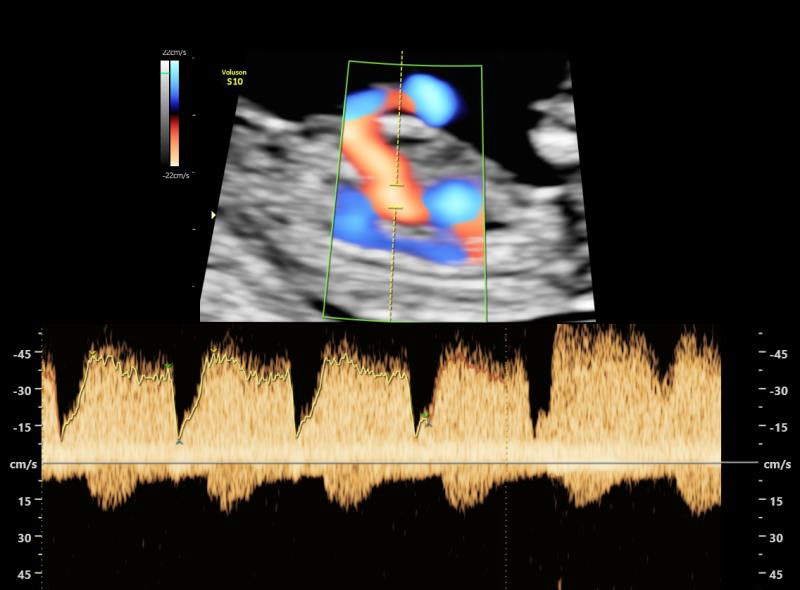

This scan is to be offered to every expecting mother irrespective of their age or prior history. It can be done only between 11-13.6 weeks of the pregnancy. Therefore, care should be taken that one does not miss this crucial scan. The baby is seen in great details to look for genetic problems. The already developed heart, spine, kidneys etc are also screened. This is usually coupled with a blood test called dual marker. Also, some maternal parameters like blood pressure and blood supply to the uterus are checked.